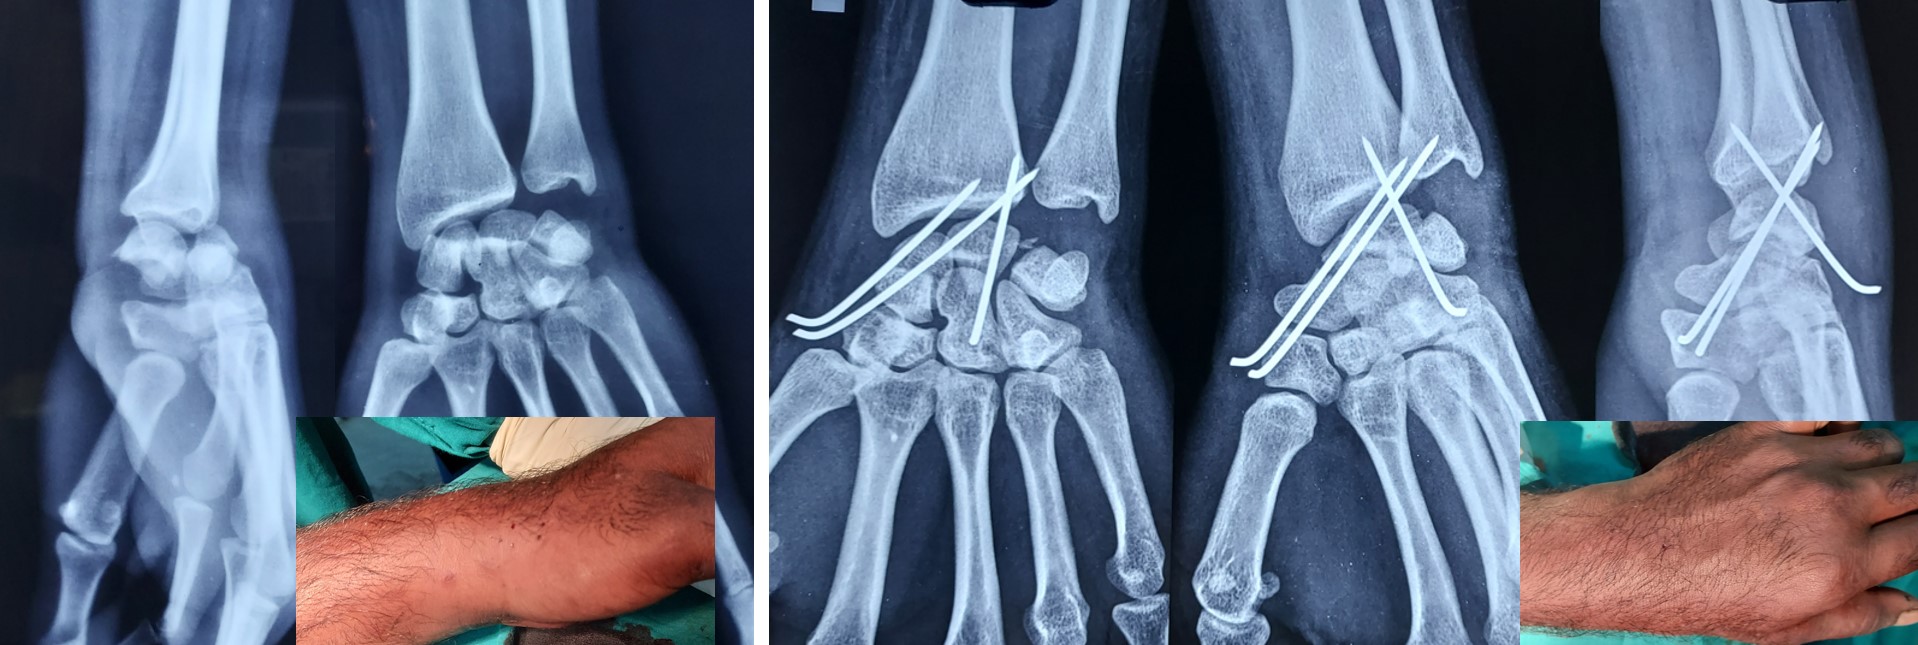

• It can be applied to any intraarticular fractures, distal end radius, elbow, ankle and foot.

• Early return to some of the personal works like writing, dressing, washing etc from the 2nd postoperative day onwards after CRPP of the fracture distal radius.

·        A Novel Method of Closed Reduction and Percutaneous Pinning with Six K-wires for Intra-articular Fractures of the Distal Radius. Anilkumar Vidyadharan, MBBS, D. Ortho, JAAOS Global Research & Reviews (June 2020-volume-4-issue 6)